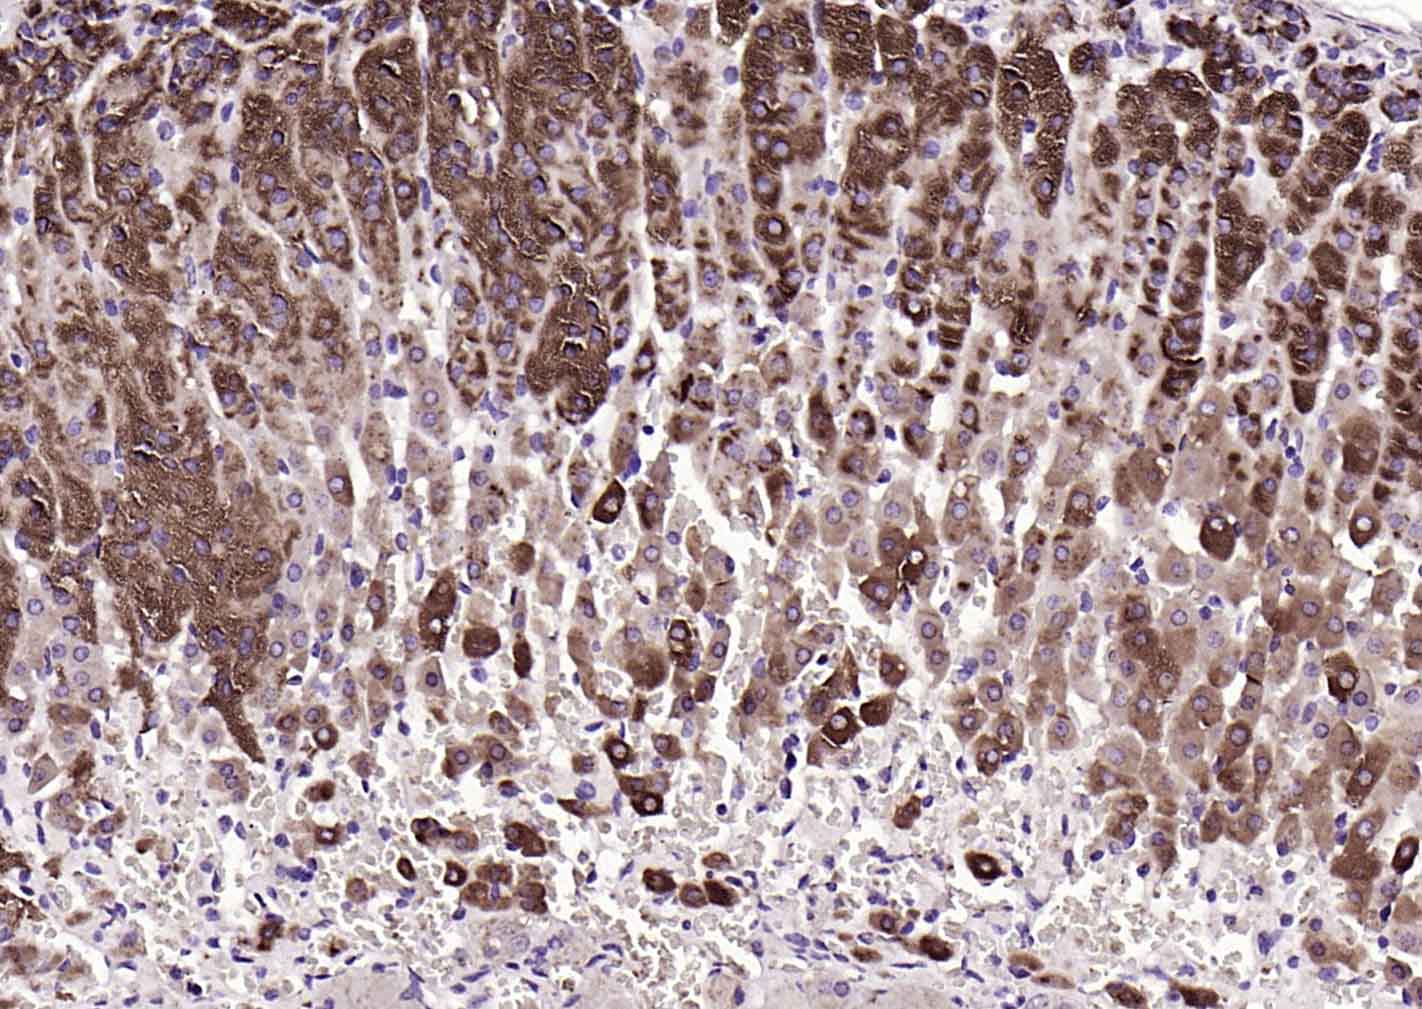

| IHC-P | Human, Mouse, Rat | Dog, Horse | 1:100-500 |